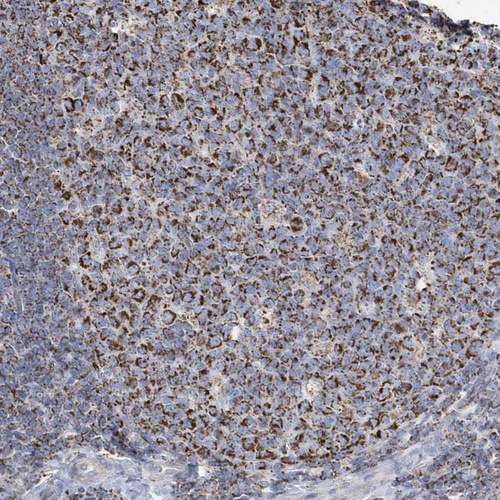

Immunohistochemical staining of human testis shows strong granular cytoplasmic positivity in cells in seminiferous ducts and Leydig cells.